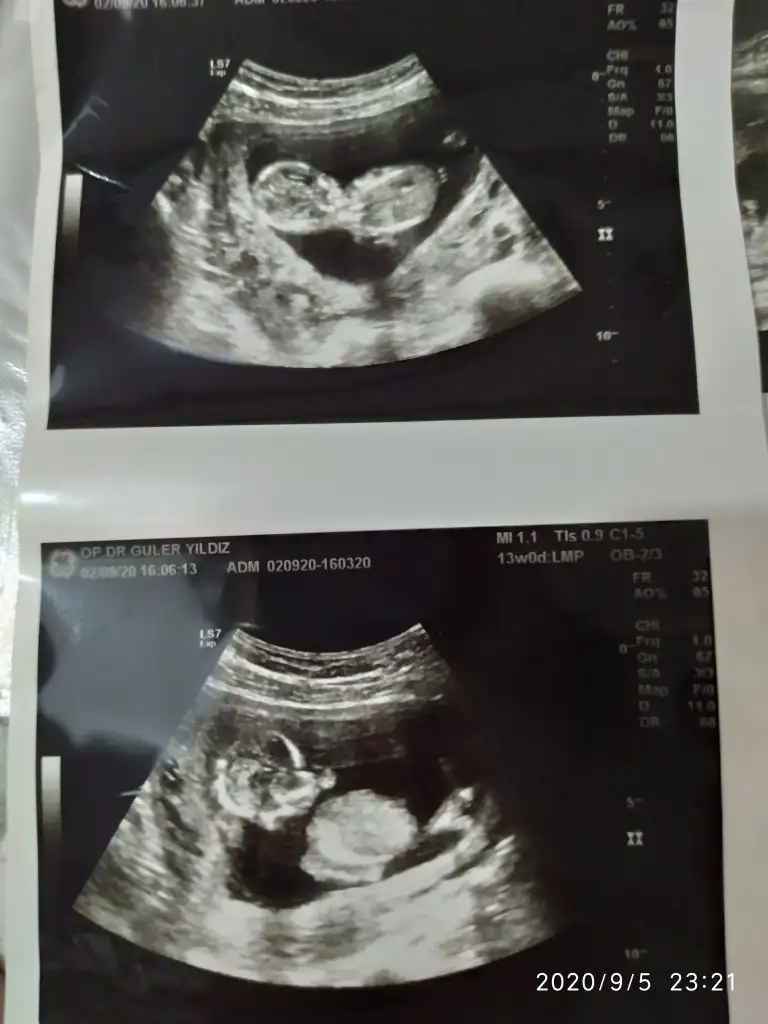

dr soylemeden siz gorun genital nub teorisi ( bebegin cinsiyeti)

Ikra meyra Ikra meyra merhaba canım 14. Hafta ultrasonundan tahmin rica etsem 😊

12+5 tahmin edebilir misiniz ? Karından ultrason Ikra meyra Ikra meyra